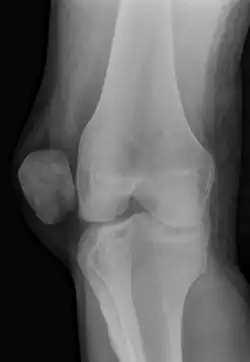

X-ray showing a patellar dislocation, with the patella out to the side.

A patellar dislocation is a knee injury in which the patella (kneecap) slips out of its normal position.[5] Often the knee is partly bent, painful and swollen.[1][2] The patella is also often felt and seen out of place.[1] Complications may include a patella fracture or arthritis.[3]

A patellar dislocation typically occurs when the knee is straight and the lower leg is bent outwards when twisting.[1][2] Occasionally, it occurs when the knee is bent and the patella is struck directly.[1] Commonly associated sports include soccer, gymnastics, and ice hockey.[2] Dislocations nearly always occur away from the midline.[2] Diagnosis is typically based on symptoms and supported by X-rays.[2]